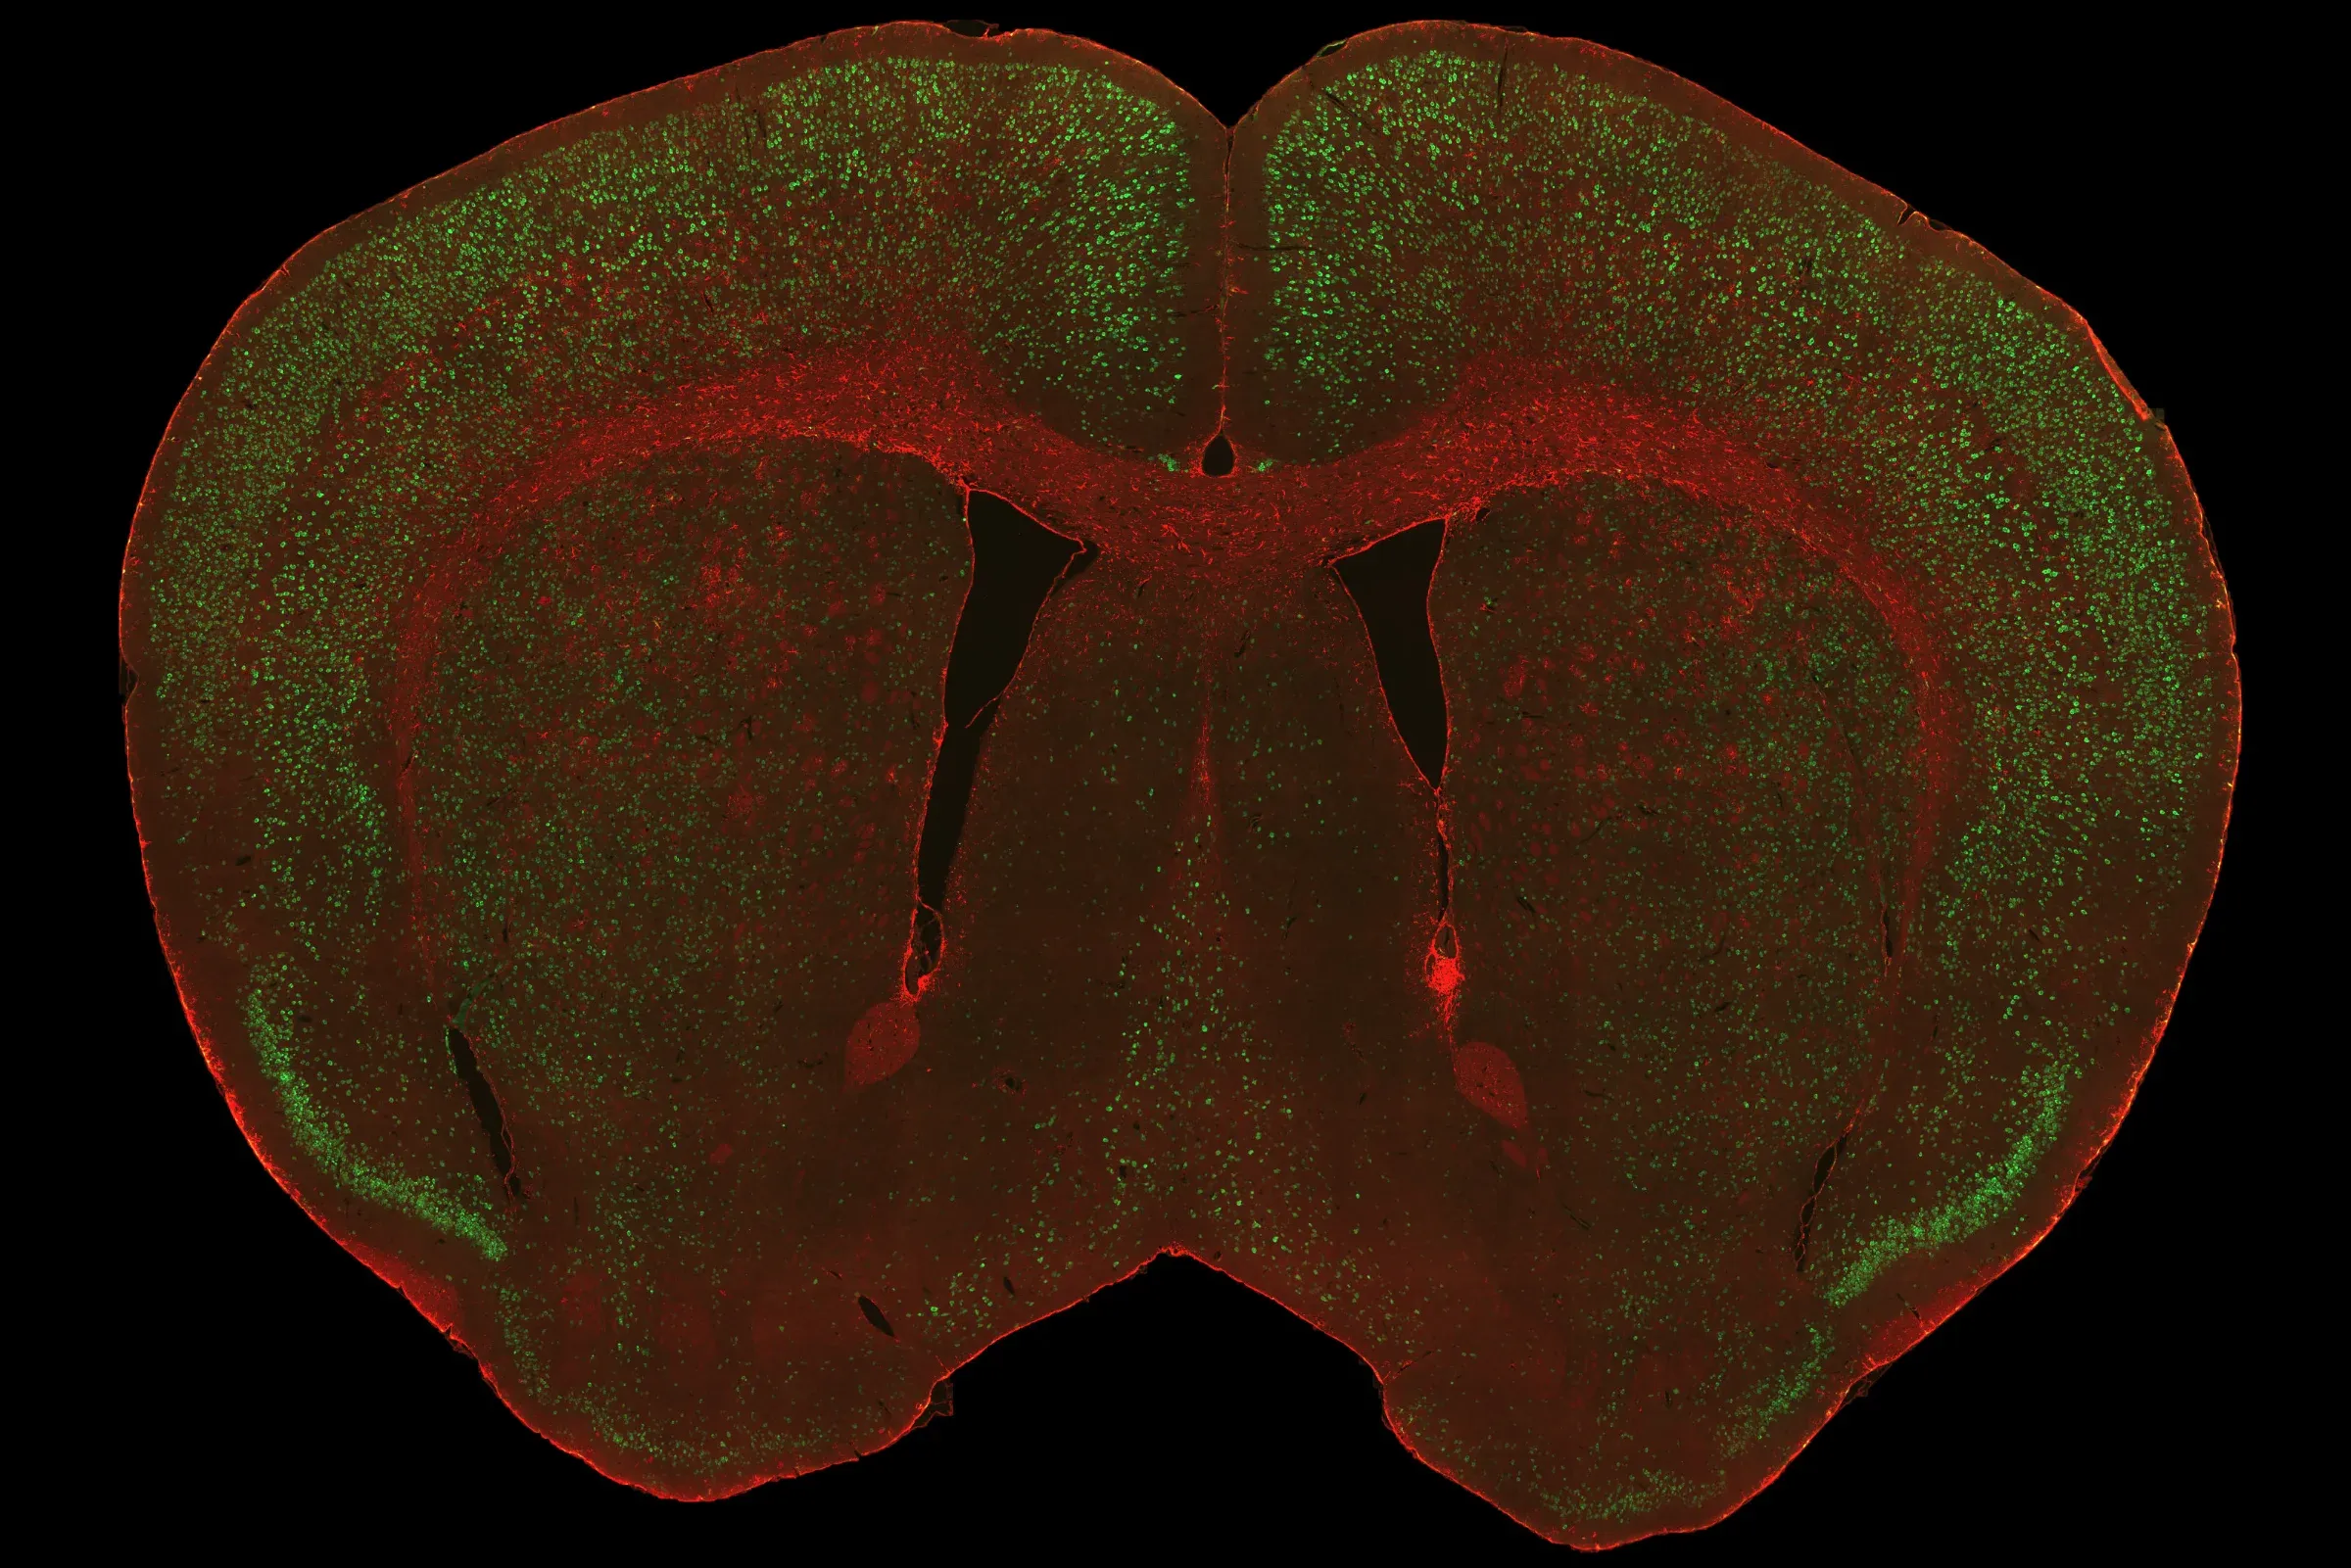

Representative visualizations of human TDP‑43 pathology in the rNLS8 mouse model, showing a coronal brain sections with TDP‑43 and astrocytes (top), TDP‑43 in cerebral cortex (middle), and mislocalization of hTDP‑43 in the cytoplasm of neurons in the motor cortex (bottom).

The cytoplasmic mislocalization of misfolded TDP-43 aggregates that characterizes human ALS can be recapitulated in the mouse brain. In this inducible transgenic mouse model, human wild-type TDP-43 with a defective nuclear localization signal (NLS) is expressed under the NEFH promoter. This model is considered one of the best ALS animal models for drug testing given its strong translational relevance.

Aggregates of misfolded proteins, such as TDP-43 and SOD1, are neuropathologic hallmarks of sporadic and familial forms of ALS. In >97% of cases of ALS, aggregates of TDP-43 are found mislocalized to the cytoplasm of neurons in the brain and spinal cord (Arnold, 2023). Phosphorylated aggregates are also typically observed. These characteristic features are readily observed in our TDP-43ΔNLS mouse models.